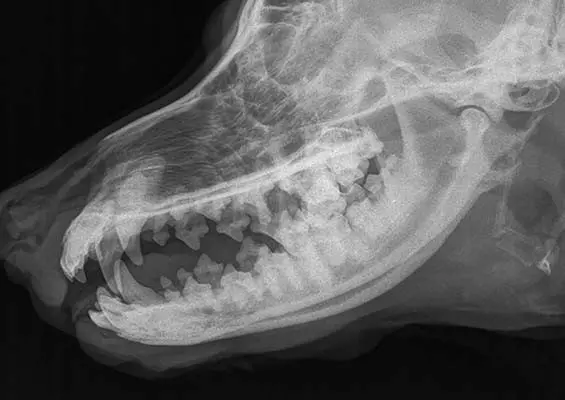

DIAGNOSTYKA

Dlaczego warto wykonywać dodatkowe badania obrazowe w diagnozowaniu chorób przewodu pokarmowego?